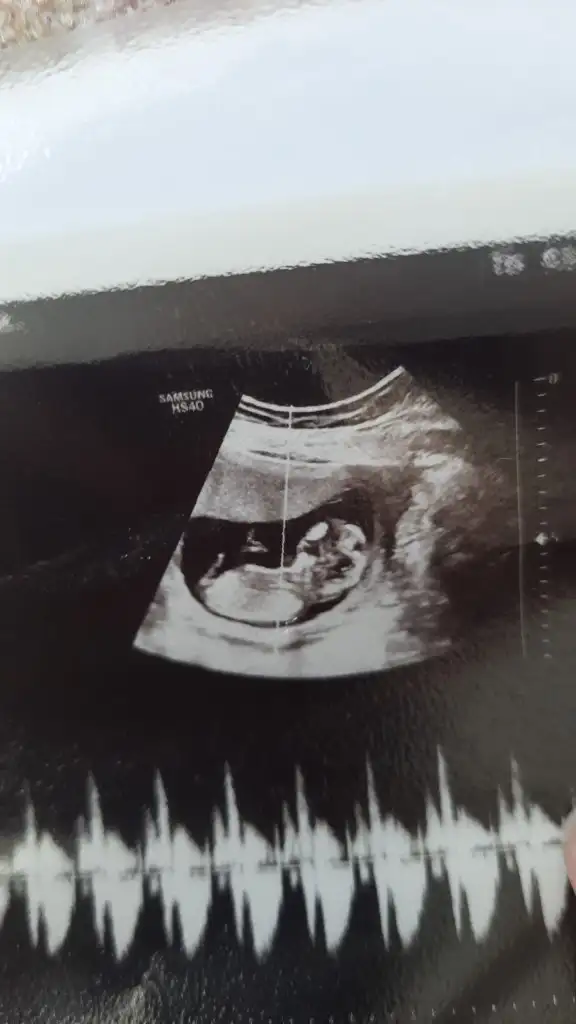

2024 Mart Anneleri Paylaşım Alanı

Bebeğimin cinsiyeti

• Ankete Katılan

289